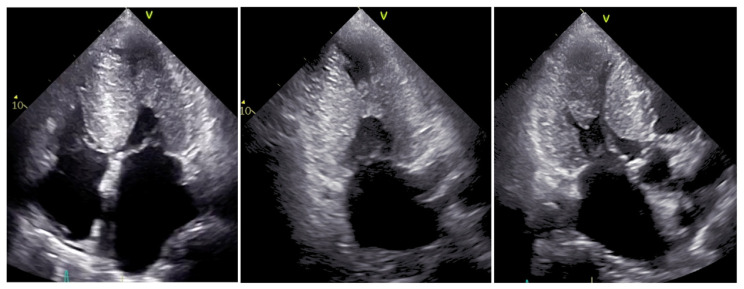

A 76-year-old man was referred to our appointment with complaints of exertional dyspnea. He had a medical history consisting of chronic coronary syndrome, hypertrophic cardiomyopathy, and an implantable cardioverter-defibrillator for primary prevention. A transthoracic echocardiogram revealed features suspicious for cardiac amyloidosis. Haematologic and genetic tests were negative, and scintigraphy was positive, confirming wild-type transthyretin amyloidosis, not eligible for tafamidis. Several months later with optimized medical therapy, he had two worsening heart failure events. This clinical case highlights the importance of differential diagnosis. Our patient had both hypertrophic cardiomyopathy and transthyretin amyloidosis, a rare association that constitutes a diagnostic and treatment challenge.

Abstract Image